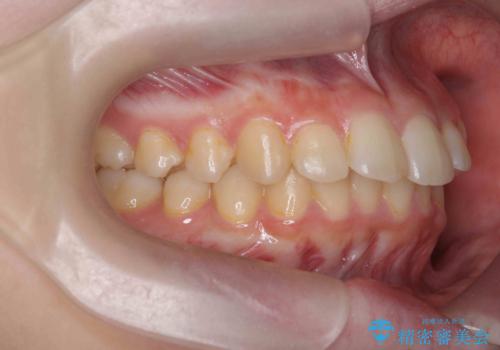

- 突出感のある、前歯の矯正治療を求めて来院されました。

軽度な突出・ガタつきを26枚・約半年の矯正治療期間で計画するインビザラインモデレートプランで治療を始めて行きます。

約半年といった短期間で、前歯の角度やガタつきを改善することができました。